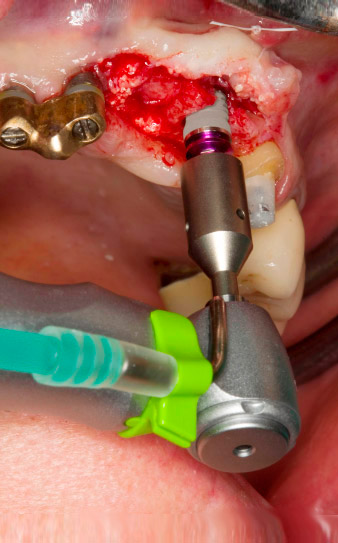

След първичното оздравяване, меките тъкани са оформени посредством базално разположения мост. Два месеца по-късно, обработваното поле е изложено на палатинална алвеоларна инцизия (Фиг 2). Размерите на алвеоларната кост са достатъчни в позиция 22. Фигури 2 и 4 показват препарацията на имплантното ложе, нарязващия винт и имплатирането, използвайки Implantmed.

Новият имплантологичен мотор е използван с подходящите обратни наконечници на W&H.

Препарацията на имплантното ложе, нарязването с винт и имплантирането са извършени с новия имплантологичен мотор Implantmed, за който авторът казва, че е успешно проектиран апарат. Производителят наистина е разработил цяла гама от технически характеристики за този апарат. Например, удобното меню в системата за навигация от сензорния екран е особено полезно. Изборът на всички функции е лесен и те удобно могат да се адаптират към спецификите на имплантологичната система и Вашите лични предпочитания. Това е приложимо за до шест потребители в по-големите практики или болници.